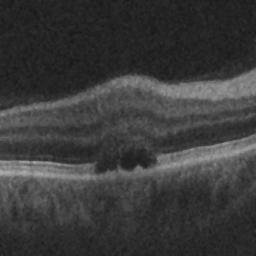

The qualitative results of the proposed system is shown in the Fig. 3. The detection task is evaluated using Area Under the Curve(AUC) metric and the segmentation task is evaluated using Dice Coefficient(DC) metric and the results are presented in Table1

| (d) De-noised OCT slice | (e)Predicted fluid region | (f)Manual fluid segmentation |

|

|

|

| (g) De-noised OCT slice | (h)Predicted fluid region | (i)Manual fluid segmentation |